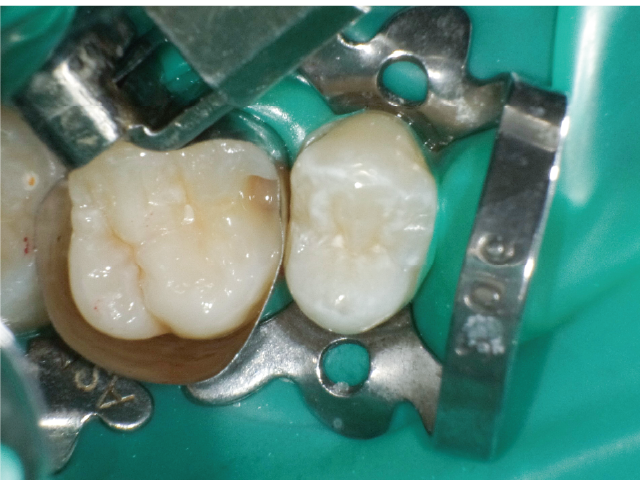

①窩洞形成段階(図1~7)

本症例では、ダイヤモンドの微粒子でコーティングされたエアースケーラーチップを窩洞形態の仕上げに使用。隣在歯の誤切削を防止し、エナメル質の切削断面を歯肉側窩縁までなめらかになるよう仕上げました。

本チップは切削時にストレスが少ない穏やかな振動のエアースケーラー専用のダイヤモンドチップで、切削部となる半球形状の面にのみダイヤモンド砥粒がコーティングされており、背面平坦部は隣在歯を削らないよう平滑になっています(図8、9)。チップの屈曲角度は110°に設定され、窩洞へのアクセスが容易な形状となっています。S67D(アングルの外側)、S68D(アングルの内側)チップは半球状の切削部位が設定され、臼歯部の近遠心両側の窩洞形成に使用が可能です。本症例では、左上6近心隣接面部の窩洞であったため、アングルの外側に半球状の切削部位が設定されている「S67D」を使用しました。これらの器具を使用することにより、頬舌側の隅角部歯質を温存した最小限の規模で窩洞形成を終了、防湿操作および隔壁の設置に移行することができました。